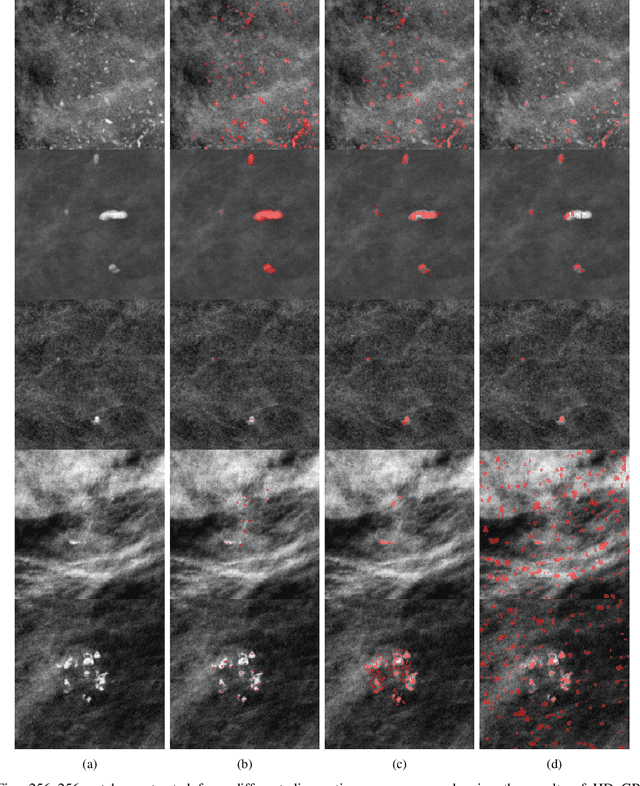

Abstract:Accurate characterization of microcalcifications (MCs) in 2D full-field digital screening mammography is a necessary step towards reducing diagnostic uncertainty associated with the callback of women with suspicious MCs. Quantitative analysis of MCs has the potential to better identify MCs that have a higher likelihood of corresponding to invasive cancer. However, automated identification and segmentation of MCs remains a challenging task with high false positive rates. We present Hessian Difference of Gaussians Regression (HDoGReg), a two stage multi-scale approach to MC segmentation. Candidate high optical density objects are first delineated using blob detection and Hessian analysis. A regression convolutional network, trained to output a function with higher response near MCs, chooses the objects which constitute actual MCs. The method is trained and validated on 435 mammograms from two separate datasets. HDoGReg achieved a mean intersection over the union of 0.670$\pm$0.121 per image, intersection over the union per MC object of 0.607$\pm$0.250 and true positive rate of 0.744 at 0.4 false positive detections per $cm^2$. The results of HDoGReg perform better when compared to state-of-the-art MC segmentation and detection methods.